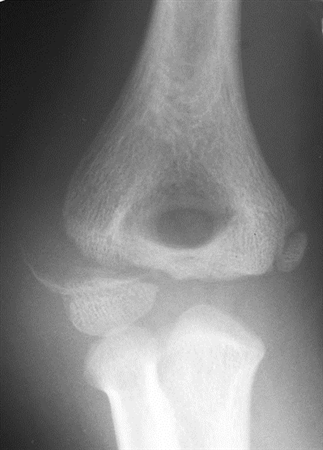

The karyotype (genetic makeup of the chromosomes) does not always predict the appearance or medical symptoms of a person with ts. Turner syndrome physical examination - wikidoc

Turner syndrome physical examination - wikidoc from www.wikidoc.org